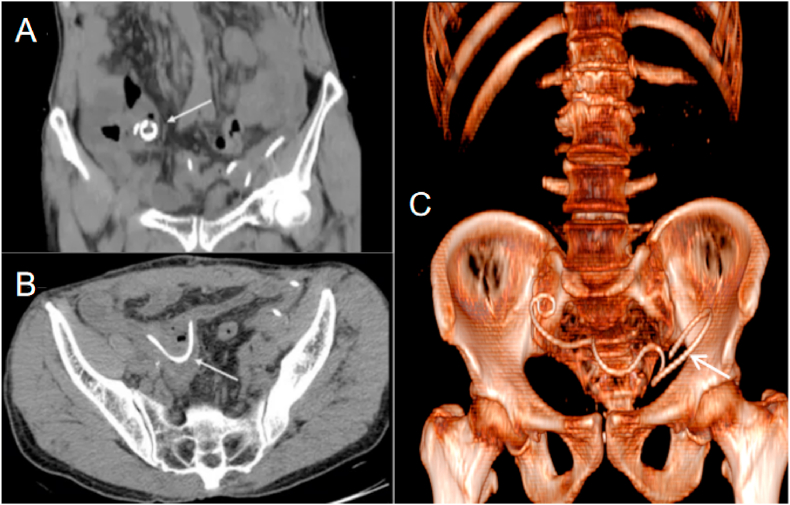

Fig. 1.

Computed tomography (CT) scan of the abdomen and pelvis shows the double-J stent's misguided.

A: Coronal reformat shows the end of the double-J stent (white arrowheads) located into the terminal ileum.

B:Transverse reformat show that the stent saw as an approximate 4mm, hyperechoic, linear intraluminal structure(white arrowheads).

C:3D-CT show a continuous complete D-J stent located in the pelvic(white arrowheads).